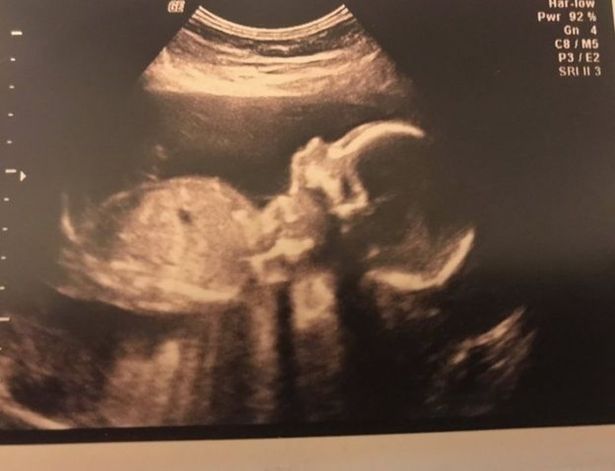

في حالة نادرة الحدوث أنجبت أم مكلومة رضيعا مقطوع الرأس خلال ولادة فاشلة، حيث تساءلت بعد سنوات من هذه الواقعة، ماذا سيكون شكل رضيعها إذا كان على قيد الحياة.

وبحسب صحيفة " ميرور"، توفي الرضيع ستيفن نجل لورا جالاتزي في عملية ولادة فاشلة في مستشفى نينويلز، بمدينة دندي الاسكتلندية في عام 2014.

وكانت الأم المكلومة بالغة من العمر 35 عاما هرعت إلى المستشفى، وهي بالاسبوع الـ25 ، حيث كان يولد طفلها قبل أوانه.

ولكن بدلًا من أن تتم الولادة بالقسم القيصري، حاول الطبيب إجراء عملية الولادة الطبيعية، مما أسفر عن نتائج مدمرة.

بشكل مأساوي، انفصل رأس الرضيع عن جسده خلال عملية الولادة، في المرة الأولى ، ما اضطر الام للخضوع لعملية جراحية لإزالة الرأس حتى يمكن تخييطه مرة أخرى على جسم ابنها.